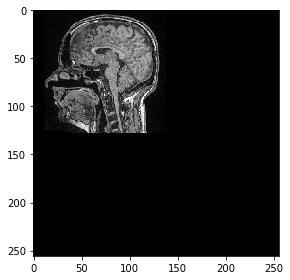

Scikit-image solo admite transformaciones 2D, por lo que seleccionamos un corte para transformarlo:

# pull image stack from GPU and pick a slice

image = np_array[100]

from skimage.io import imshow

imshow(image)

<matplotlib.image.AxesImage at 0x25a6cff0d30>

../_images/b9ec53895c9942461dd35e1b88b95a9557441ceb09c074bd865d8bb6ddfdb74b.png